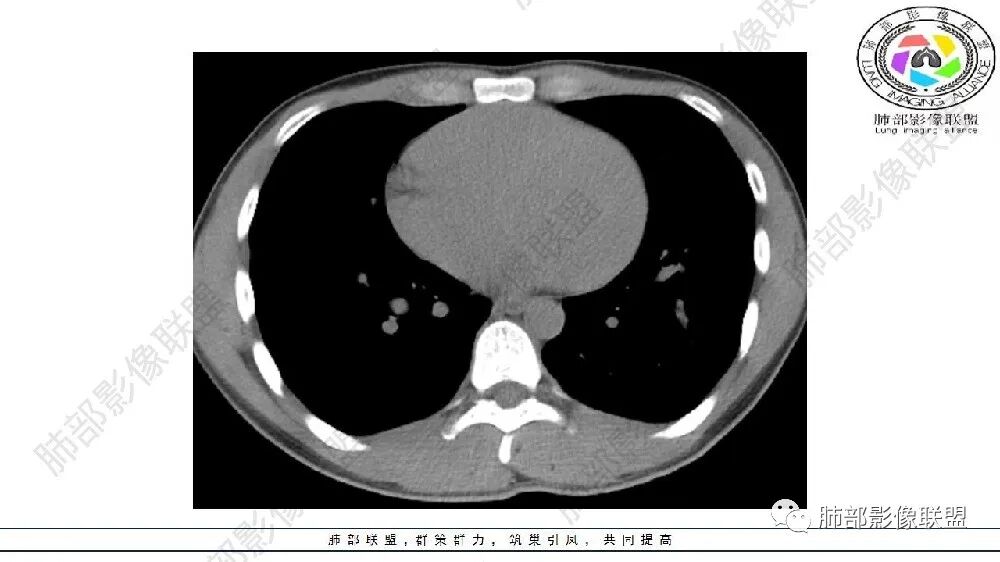

年轻男性,左肺下叶肺动脉明显增粗特点(与对侧比较,降主动脉旁胸膜下分布粗大血管征、左肺下叶肺气囊腔和磨玻璃影,首选肺隔离征,与血管畸形鉴别,病理生理特点:体循环异常分支(压力高)与左肺下叶肺动脉成异常交通。血管血流倒灌左肺下叶表现。

连续的看这些管状影与肺动脉好像没有连续性,不知道是否与主动脉相连,附近高密度影,提示感染。

可见囊状影、管状影,附近血管明显增粗,似乎与肺动脉不相连

1、需要明确血管与主动脉关系,如果相连--隔离症

主要观察左下叶病灶,应该是做过手术或明确了血管与主动脉关系,就目前的表现而言还是更支持隔离:肺动脉、支气管分支似乎没进入病灶区,这是隔离或体动脉供血的特点。囊腺瘤样畸形,按理肺动脉及支气管照样进入这个区域才对;需要重建观察这些血管、支气管才好明确